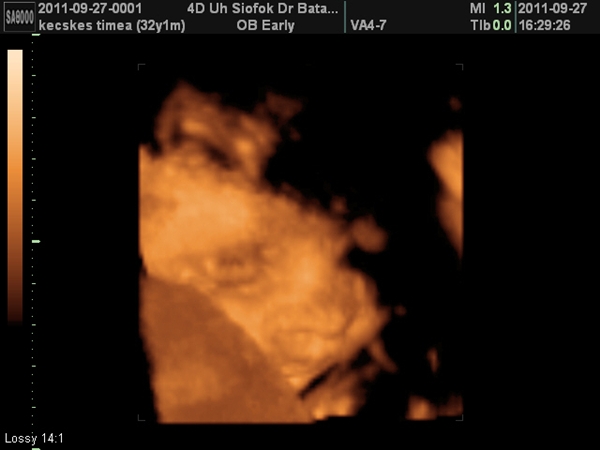

Csongor 28 hetes

Tegnap voltam orvosnál, most Siófokon, mert ide kaptam időpontot, így alakult. A siófoki rendelője sokkal jobb a dokimnak, mint a fehérvári, ha az útiköltség árával olcsóbb lenne a rendelés, csak oda járnék :) Sokkal jobb az ultrahang képe, mint itt, és 3D-be is át tud váltani. Amúgy nem mentünk volna külön 3(4)D-s ultrahangra, de ha már így volt lehetőség, azt kihasználtam. Csongor majdnem irányban helyezkedik már el, csak kicsit jobbra van fordulva, mert ott a méhlepény, és abba fúrja bele az arcocskáját :) Biztosan olyan baba lesz, ha kibújik, aki szeret majd pelusozni, arcát párnába fúrni :). Azonkívül jó nagy baba is, mondom az adatait, tegnap 27+5 volt a kora:

Buksi keresztben (BPD): 7,52 cm, 30+1-nek felel meg (azt mondja a doki: hát Timi, meg kell szülni... mondtam neki, nem volt ilyen kérdés :D)

Fejkörméret: (HC): 26,61 cm, 29 hetesnek felel meg

Haskörméret (AC) 24,77 cm, 29 hetesnek felel meg

Combcsont (FL) 5,31 cm, 28+1-nek felel meg. Rövid lábú, nagy fejű? :D De még a lába is hosszabb, mint a korának megfelelő. Ja, és a talpa 5,6 cm, nagyobb, mint a combcsont, hát hogy fogunk ennek a gyereknek cipőt venni? :D A becsült súlya 1276 gramm, ez 28+3-nak felel meg. A gép számításai szerint, ha kivárja a 40 hetet, akkor 4 kiló körüli lesz, ha viszont ezekkel a mostani adatokkal átlagos baba szeretne lenni, akkor 10 nappal előbb kéne megszületnie. Részemről rendben :)

Szóval mondják, és én is hiszem, hogy nem függ össze a baba mérete a pocak méretével, én inkább abban hiszek, hogy a harmadik gyerekkel és kis korkülönbséggel látványos a növekedés, azért nem véletlenül érzem, látom a pocakomat nagynak amellett, hogy egyelőre mindössze 2,8 kilót híztam. Egyszer már tartottam itt, de aztán fogytam egy kilót. Mindenesetre pár kép a méhlepénybe bújó Csongor babáról: